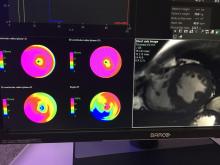

Preventing contrast induced nephropathy and managing patients with chronic kidney disease remain major challenges in the cardiac catheterization lab. In recent years, contrast supply shortages have presented a new challenge to care delivery. When considering these challenges, and as quality metrics in our labs face more scrutiny, there are existing technologies and best practices such as a variable rate contrast delivery systems and HD IVUS that can be used to manage workflow and improve patient outcomes.

The ACC Interventional Council’s recent statement recommending that intracoronary imaging be a routine part of clinical practice further reinforces the need for adoption of intracoronary. Using a case-based approach, the faculty will demonstrate how to use the ACIST CVi contrast delivery system, HDi high definition IVUS and diagnostic and post-PCI physiologic assessment to reduce contrast usage, improve AKI rates and deliver optimized patient outcomes.